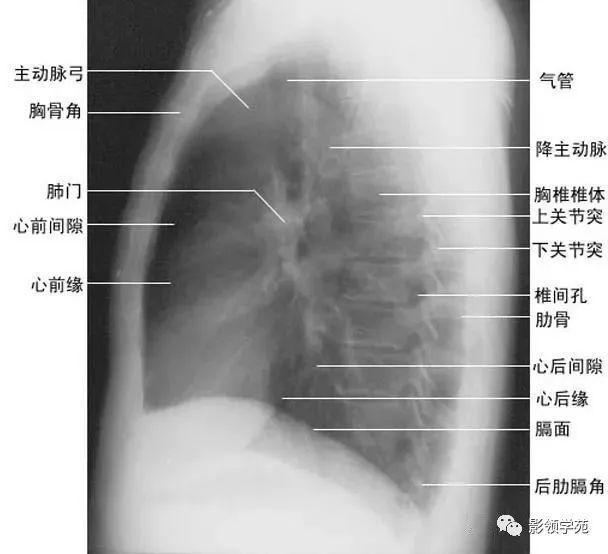

2、侧位肺门 侧位胸片上,两饲肺门阴影大部分重叠,若以侧位气管轴线为界,右肺门略信其前下,左肺门大部分在其后上。侧位肺门影前缘为右上肺静脉干形成的椭圆形阴影,前后径为2cm左右;中间纵行透亮区为气管及气管分叉,其内圆形透亮影表示支气管开口,右侧在上,左侧居下;后上缘为左肺动脉弓,下缘由两下肺动脉构成下行的树枝状影。因此,侧位肺门影似一尾巴拖长的“逗号”(如上右图):

(四)左侧位

心影从后上向前下倾斜,心前缘下段为右心室前壁,上段则由右心室漏斗部与肺动脉主干构成,再苣上为升主动脉前壁,直向上走行。这些结构与翦髓壁之间的三角形透亮区称为胸骨后区。心后缘上中段由左心房构成,下段则由左心室构成。心后下缘、食管与膈之间的三角形间隙,为心后食管前间隙(如下图)。